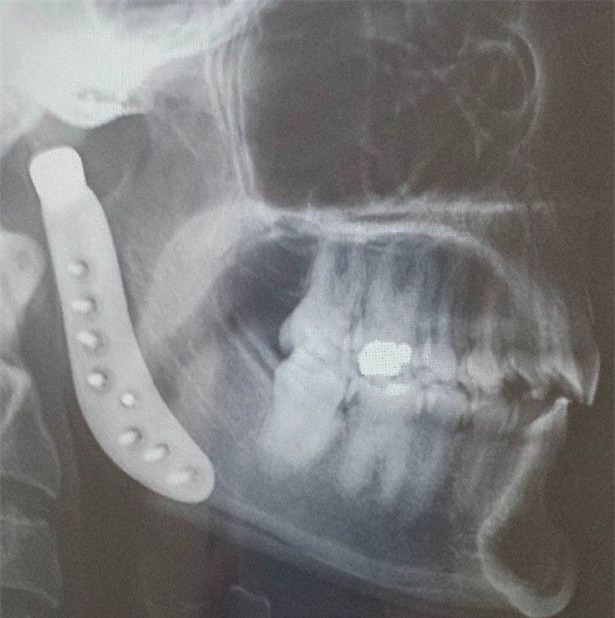

Ngay sau đó, cô quyết định đến nha sĩ kiểm tra. Bác sĩ chẩn đoán Tamara bị lệch đĩa đệm khớp thái dương hàm bên phải. Có vẻ như chiếc đĩa đệm này đã lệch từ rất lâu rồi, và giờ nó biến thành viêm thoái hóa khớp. Cô đã trải qua một thủ thuật để sửa hàm nhưng mọi chuyện còn tồi tệ hơn.

Sau đó, bạn bè cô đã lập một tài khoản vận động từ thiện có tên là GoFundMe để kêu gọi sự trợ giúp của mọi người. Năm 2013, Tamara trải qua cuộc phẫu thuật kéo dài 5 giờ đồng hồ để thay thế hàm. Nó tiêu tốn 17.000 USD (khoảng 400 triệu đồng) . Tuy nhiên, chỉ vài tháng sau đó, cô còn cảm thấy đau đớn hơn và xuất hiện nhiều biến chứng lạ trên da.

"Năm 2016, những cơn đau ngày càng kinh khủng hơn và tôi biết mình phải thay thế hàm lần nữa", Tamara chia sẻ. May mắn lần này, khớp hàm giả bằng titanium không khiến cô dị ứng; tuy nhiên, bà mẹ này đang phải đối mặt với nguy cơ sức khỏe khác do ảnh hưởng lâu dài của các chất có trong khớp hàm giả khiến cô bị dị ứng trước đó.